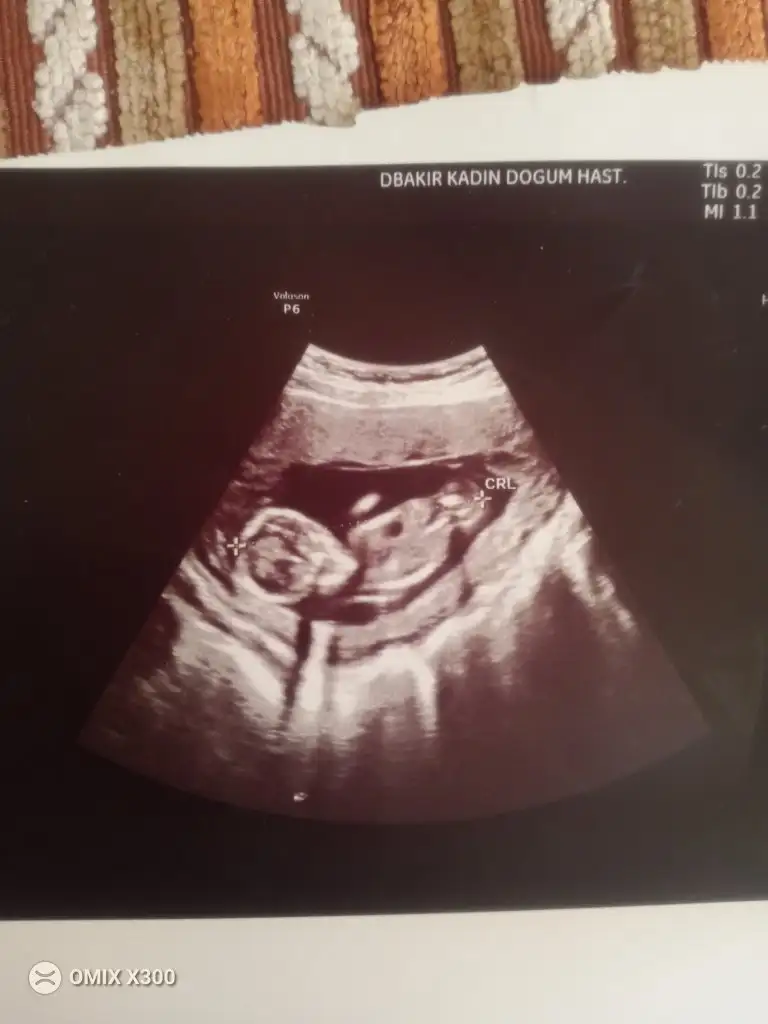

bize de tahminde bulunur musunz doktorumuz tahmin etti ama net değil dedi baska bı doktora gittik o da belli değil daha dedi

Kız benceEki Görüntüle 3501296 banada bakarmisiniz burda 12 haftalik 15 haftalik oldu daha belli degil